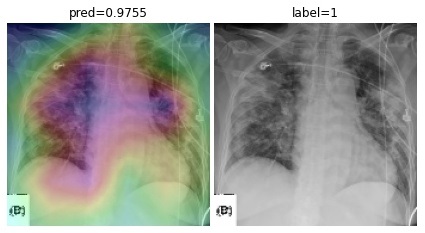

To overcome the aforementioned issues and force the model’s attention to the correct regions of interest (ROIs), we introduce the COVID-CXNet. Our model is initialized with the pretrained weights from CheXNet. A dataset of 3,628 images, 3,200 normal CXRs and 428 COVID-19 CXRs, are divided into 80% as training-set and 20% as test-set. Batch size is set to 16, rather than 32 in previous models, regarding memory constraints. Grad-CAMs of the COVID-CXNet for random images are plotted in Fig. 15.

Refer to caption

Figure 15: Grad-CAM visualization of the proposed model over sample cases

More Grad-CAMs are available in Appendix A. Heatmaps are more accurate than previous models, while an accuracy of 99.04% and an f-score of 0.96 are achieved. Table 3 is the confusion matrix of the proposed model.